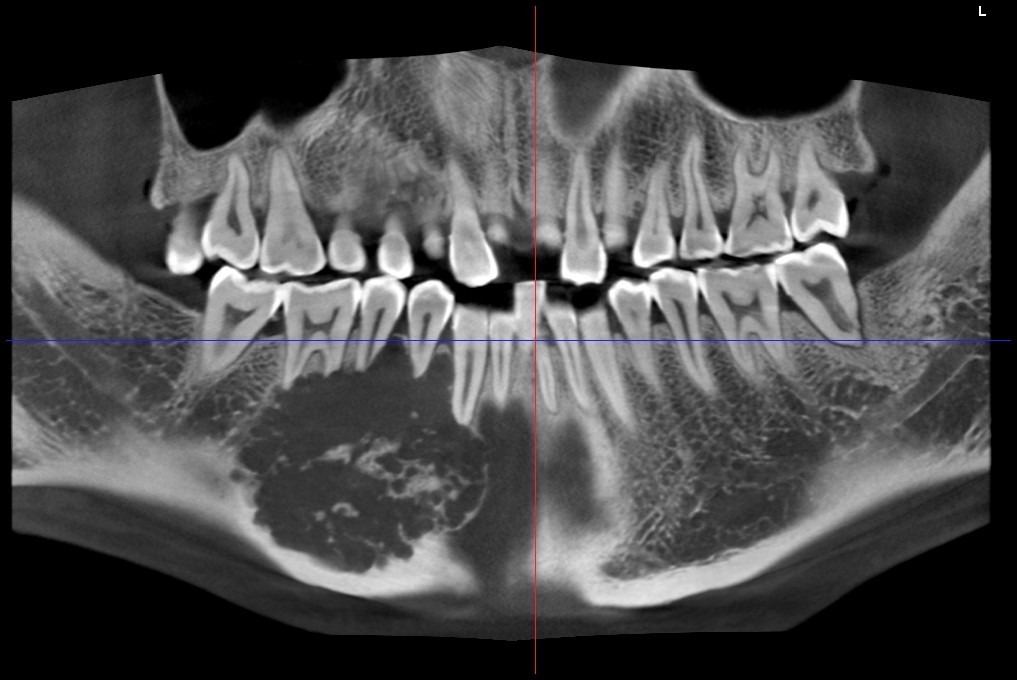

颅颌面CBCT

诊断范围涉及牙体牙髓病、牙周病、阻生牙/多生牙定位、种植牙术前CT评估分析、颞下颌关节CT诊断分析、,颌骨及涎腺疾病、颌面发育畸形、正畸治疗辅助诊断等大部分颌面部疾病,为临床医疗提供强有力的支持。